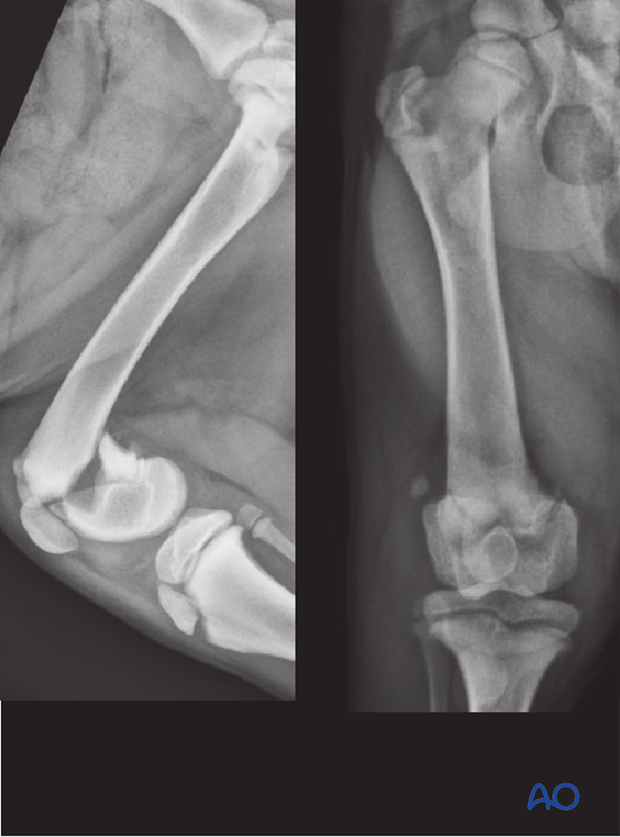

Radiographs show a Salter-Harris 2 fracture of the distal femoral physis in a three-month-old female golden retriever.